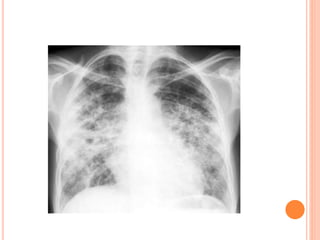

This document summarizes aspergillosis, including invasive pulmonary aspergillosis (IPA), chronic necrotizing aspergillosis (CNA), and aspergilloma. Aspergillus is a common mold that can cause a variety of pulmonary diseases. IPA predominantly affects immunocompromised patients and presents as pneumonia. Diagnosis involves tissue biopsy, galactomannan testing, and imaging. Voriconazole is recommended treatment. CNA occurs in patients with underlying lung disease and is characterized by slow lung tissue invasion. Itraconazole is effective treatment. Aspergilloma involves a fungus ball in a pre-existing lung cavity.